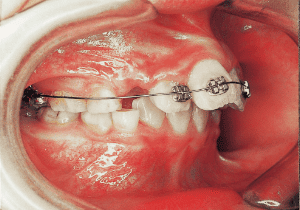

17 At start of full bracket treatment 5-18-’92

18 Treatment progress 4-11-’94

In the maxilla, insufficient space for canine eruption was inevitable, necessitating extraction as part of the treatment plan. The maxillary first premolars on both sides were extracted during routine observation to create space for canine eruption (14). Eventually, the canines erupted and settled into relatively favorable positions (15,19,20). In the mandibular dentition, crowding was also present, leading to extraction of the mandibular first premolars on both sides. Treatment with full bracket was then initiated (17).